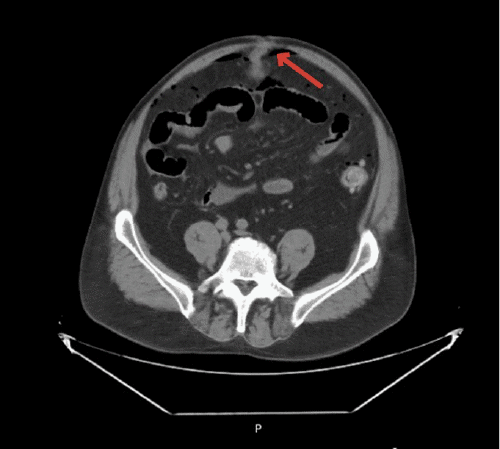

Figure 1. CT Scans Demonstrating Meckel's Diverticulum. Published with Permission

A) Abdomen axial view with Meckel’s diverticulum present in hernia sac protruding through fascia (arrow)

A 67-year-old man presented to the emergency department with the chief complaint of worsening abdominal pain, nausea, and vomiting over the course of one day. The patient reported some mild heavy lifting the day before but had minimal pain, with a new bulge noted near his umbilicus. On physical exam, the patient was found to have a very distended abdomen with focal tenderness in the periumbilical region. The patient's CT scan showed a large amount of free air with a small umbilical hernia. Before taking the patient to the OR, he asked, "Could I have a Meckel's diverticulum causing my problems? My son had this same surgery performed two years ago. He had a bleeding Meckel's diverticulum."